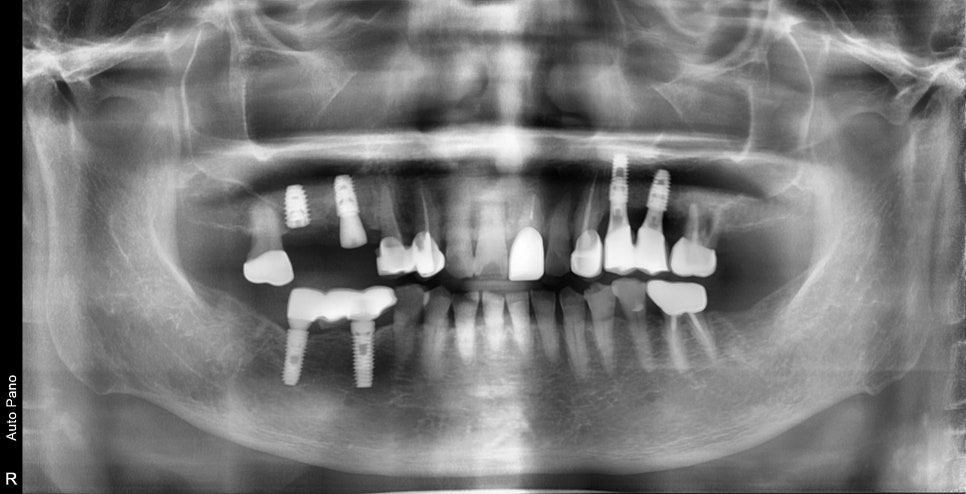

가장 안 좋은 치아만 먼저 발치를 하면서 조금 불편한 치아는 일단 지켜보기로 했습니다

염증이 심한 곳은 발치 후 회복되기까지 기다린 후 수술을 했기 때문에

좌우 치료 기간이 다를 수밖에 없었습니다.

반대쪽 치아를 완성하여 식사에 불편함이 없게 만들어드린 후

문제가 심했던 부분도 치아머리까지 완성이 된 상태입니다.